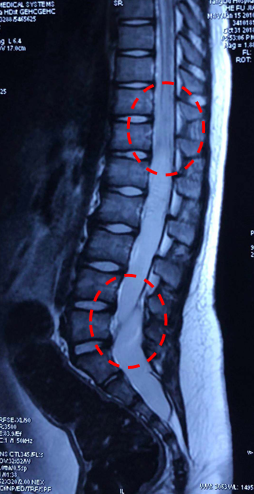

男,8岁大小便失禁伴双下肢肌力下降25天小便失禁为突出症状诊断:骶管囊肿、脊髓圆锥中央管扩张?表皮样囊肿?